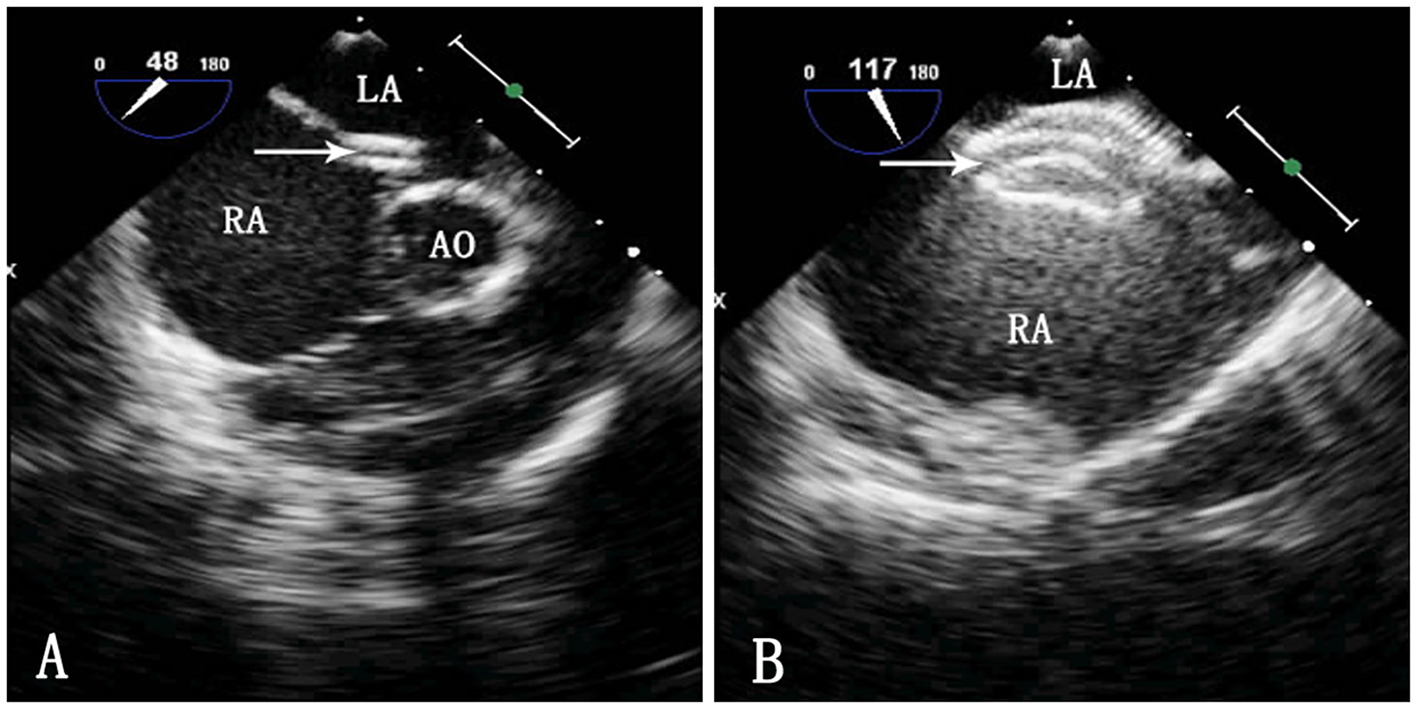

Figure 2

TEE image during ASD occlusion. LA, left atrium; RA, right atrium; Ao, aorta. (A) Passing of the sheath through the ASD. The arrow indicates the delivery sheath. (B) Morphology of the occluder after release. The arrow indicates the occluder.